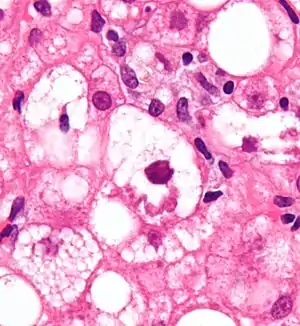

Micrograph showing a Mallory body. Original magnification 400X. H&E stain.

Mallory bodies are highly eosinophilic and thus appear pink on H&E stain. The bodies themselves are made up of intermediate cytokeratin 8/18 filament proteins that have been ubiquitinated, or bound by other proteins such as heat shock proteins, or p62/Sequestosome 1.[5]